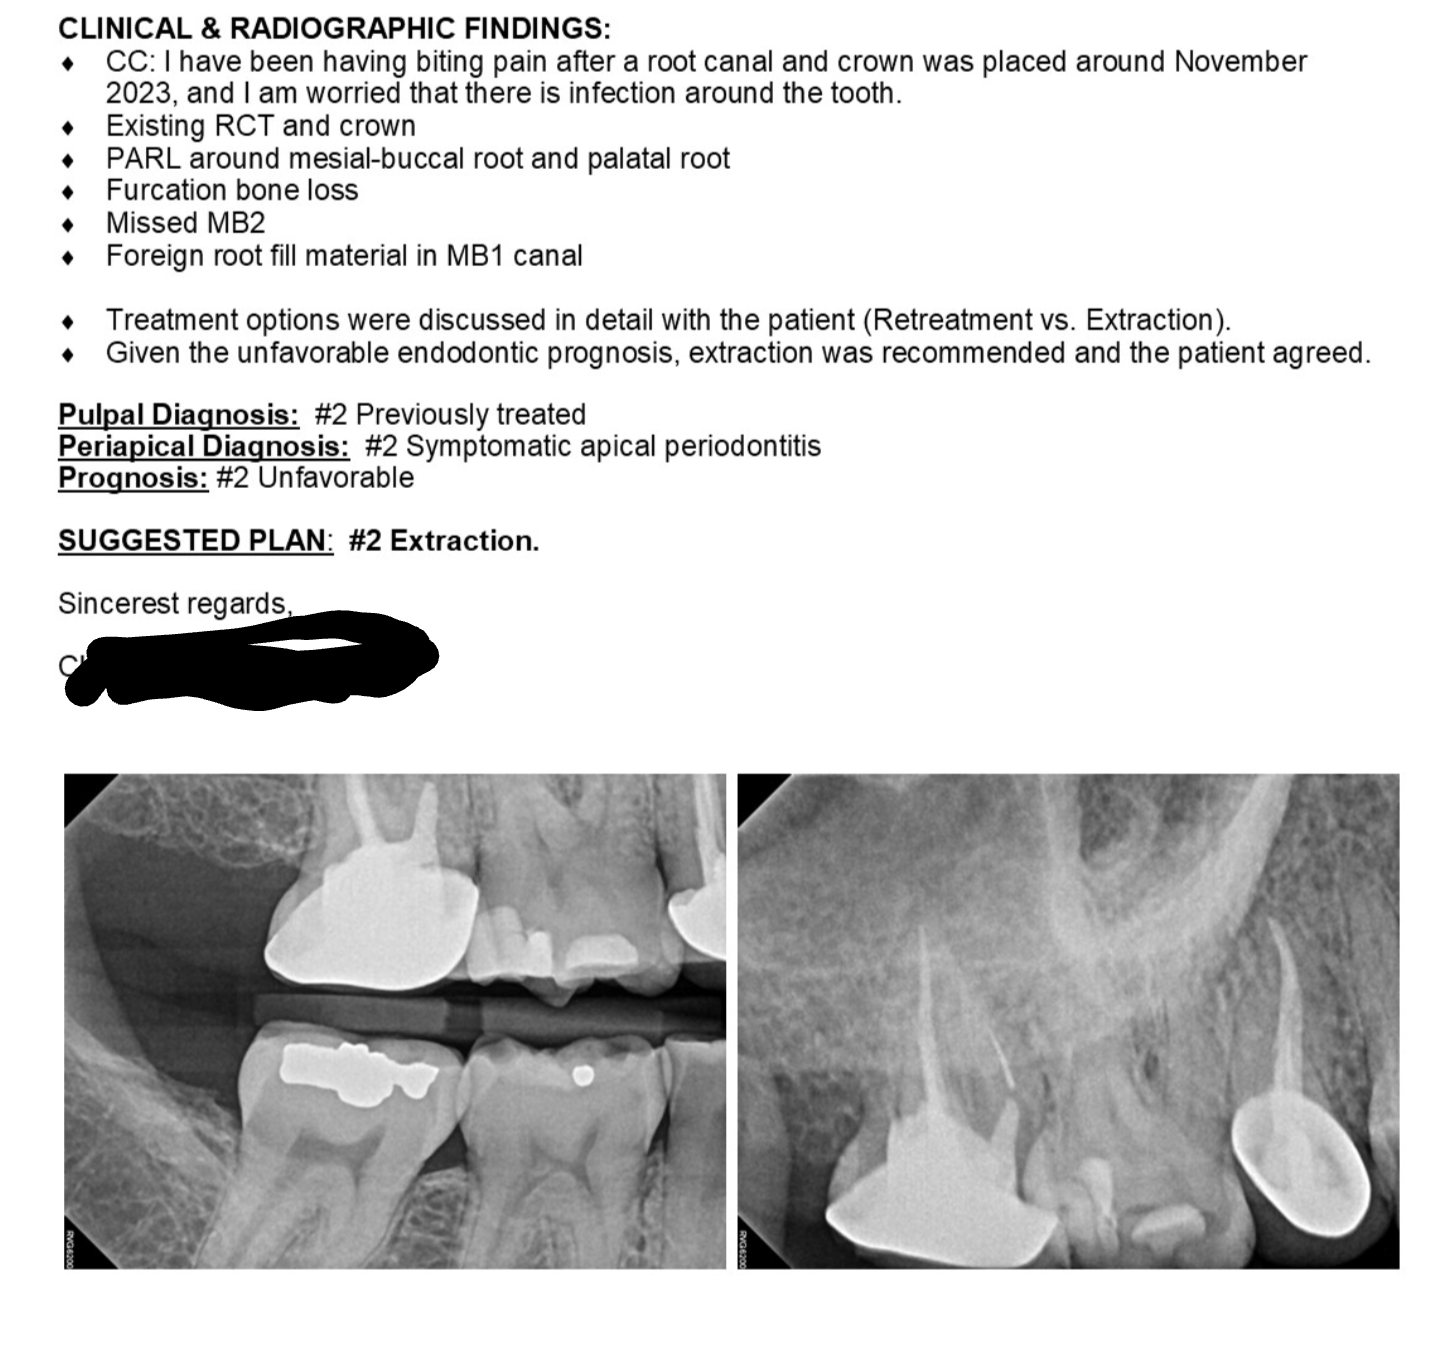

Root canal treatment failed (xray). Should I go for retreatment or Failed Root Canal Tooth Extraction According to the american association of endodontists, there are a few potential causes for a failed root canal, including: Retreatment, extraction along with a dental implant, and apicoectomy are all choices available to your endodontist. Learning the signs and symptoms of a failed root canal can help you get treatment and successfully save your natural tooth. Root canal failure means. Failed Root Canal Tooth Extraction.